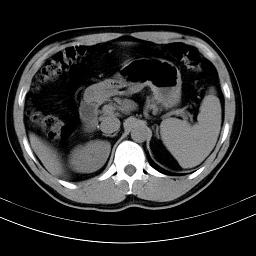

标题: CT18388:肝脏膈肌间隙内大量脂肪密度影 [打印本页]

标题: CT18388:肝脏膈肌间隙内大量脂肪密度影

是脂肪不是气体,有时候会碰到这样的病人,脂肪过多吧。

腹腔脂肪沉积过多

膈下脂肪沉积。

考虑膈下脂肪沉积。

激素治疗的病人容易脂肪沉积